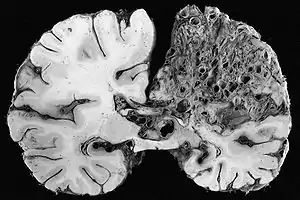

Neuropathology is the study of disease of nervous system tissue, usually in the form of either surgical biopsies or sometimes whole brains in the case of autopsy. Neuropathology is a subspecialty of anatomic pathology, neurology, and neurosurgery. In many English-speaking countries, neuropathology is considered a subfield of anatomical pathology. A physician who specializes in neuropathology, usually by completing a fellowship after a residency in anatomical or general pathology, is called a neuropathologist. In day-to-day clinical practice, a neuropathologist is a consultant for other physicians. If a disease of the nervous system is suspected, and the diagnosis cannot be made by less invasive methods, a biopsy of nervous tissue is taken from the brain or spinal cord to aid in diagnosis. Biopsy is usually requested after a mass is detected by medical imaging. With autopsies, the principal work of the neuropathologist is to help in the post-mortem diagnosis of various conditions that affect the central nervous system. Biopsies can also consist of the skin. Epidermal nerve fiber density testing (ENFD) is a more recently developed neuropathology test in which a punch skin biopsy is taken to identify small fiber neuropathies by analyzing the nerve fibers of the skin. This test is becoming available in select labs as well as many universities; it replaces the traditional nerve biopsy test as less invasive.